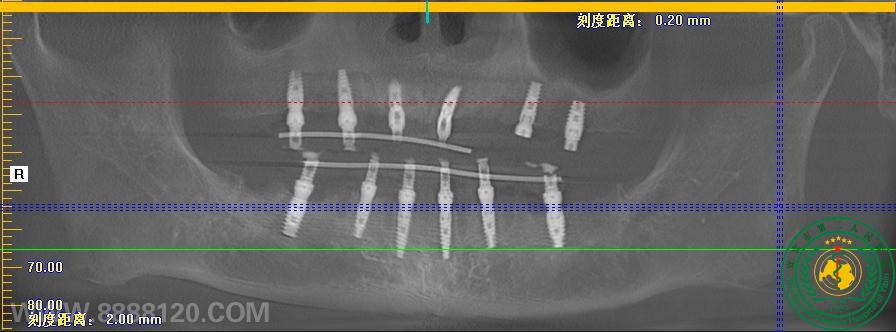

当天种牙当天用,口腔科开展全口种植即刻负重手术

当天种牙当天用,口腔科开展全口种植即刻负重手术31748